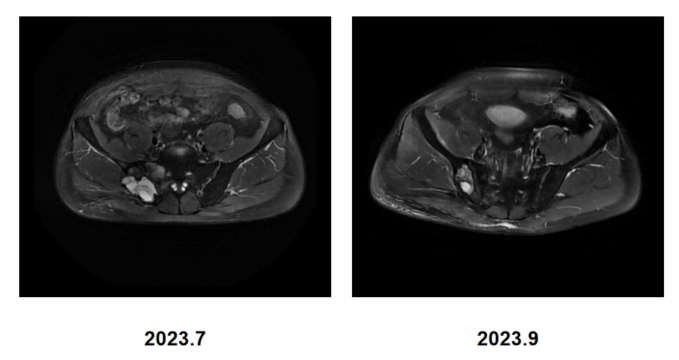

5)后续维持治疗与随访:2023年9月,MRI示骨盆仍有多处骨转移,右侧骶骨范围缩小,余同前。原本问题较为严重的髂骨病灶在放疗、免疫联合化疗、骨保护治疗的综合治疗下取得了良好的治疗效果,病灶大幅退缩,患者行动能力得到恢复;CT示右肺上叶肿瘤较前退缩,周围多发炎症较前减轻。右锁骨上淋巴结较前缩小。余双肺多发小结节,较前减少。两肺门及纵隔小淋巴结较前缩小。

图片4.png

图4. PD-1联合培美曲塞、地舒单抗治疗2月后MRI结果